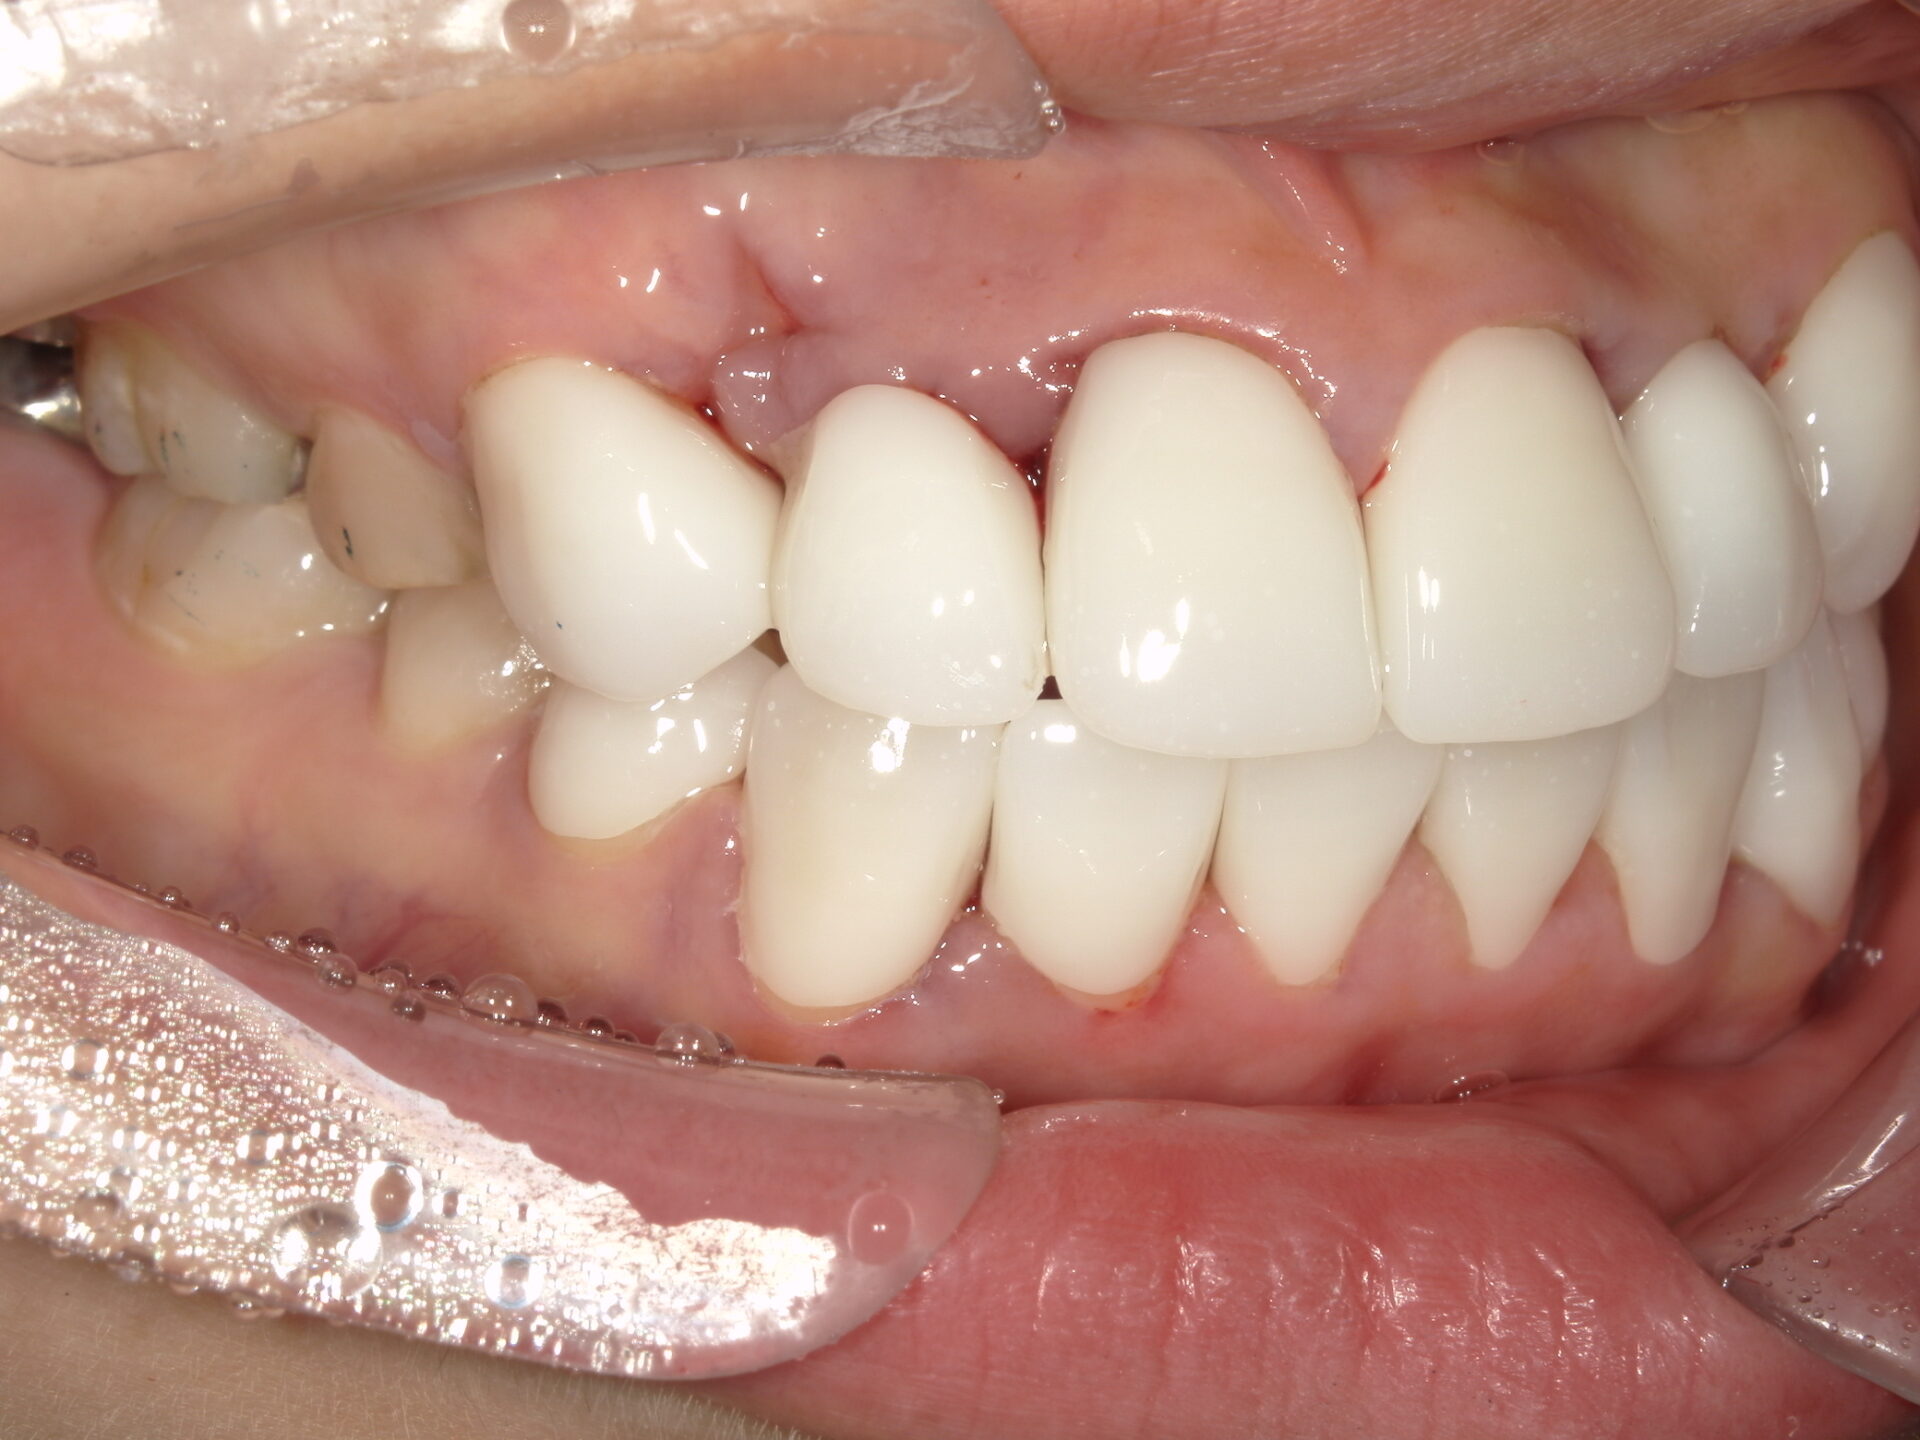

患者さんの年齢 20代 女性 症状 八重歯がコンプレックス、白い歯を入れたい 治療内容 セラミック治療 費用 費用150万(税抜) 治療期間・回数 治療期間1ヶ月・通院回数3回 メリット 治療期間・回数が少ない デメリット・リスク 術後知覚過敏が起こる事ある - セラミック治療